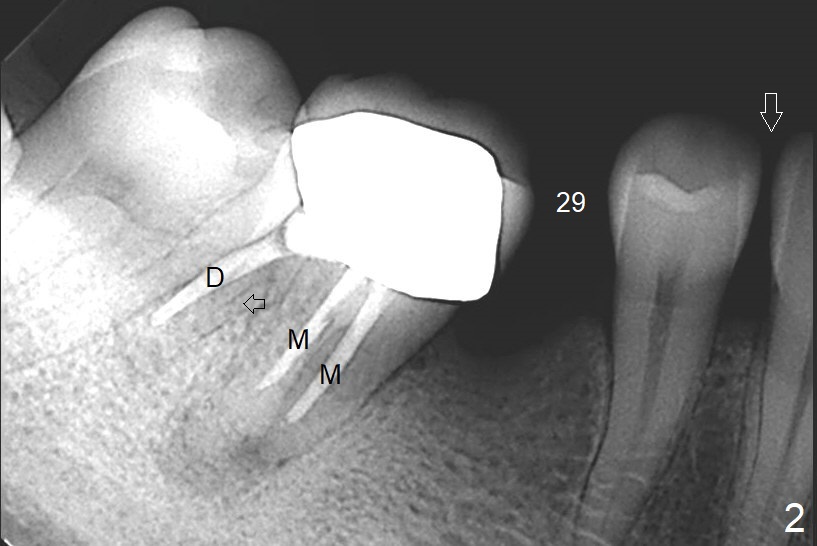

A 41-year-old slender woman returns for #29 and 30 implants (Fig.1,2) because of a fistula mesiolingual of #30 (Fig.3 arrowhead) several years post RCT. There is no deep pocket at #30. In fact the distolingual canal is missing (Fig.2 (black arrow),3 (DL)). RCT retreatment should solve apical periodontitis. Due to long term of missing #19 and 29, the mesiodistal space is limited with diastema between #28 and 29 (Fig.1, 2 (white arrowhead)). Limited ortho appears necessary prior to, during or post implantation. The ridge at #19 and 29 is not only narrow, but also short. It seems appropriate to place short 2- and 1-piece implants, respectively (Fig.5,4). As a matter of fact, there is open margin of the crown at #30 (data not shown). If the crown is to be removed prior to RCT, implantation is conducted before ortho, since the provisional can be made narrow mesiodistally.